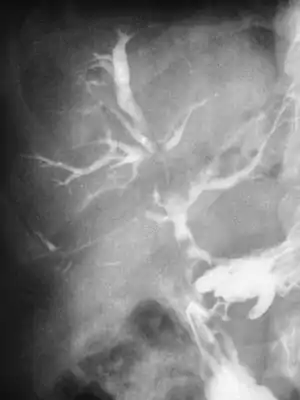

- (K83.3) Fistula of bile duct

- Biliary fistula: connecting the bile ducts to the skin surface, often caused by gallbladder surgery